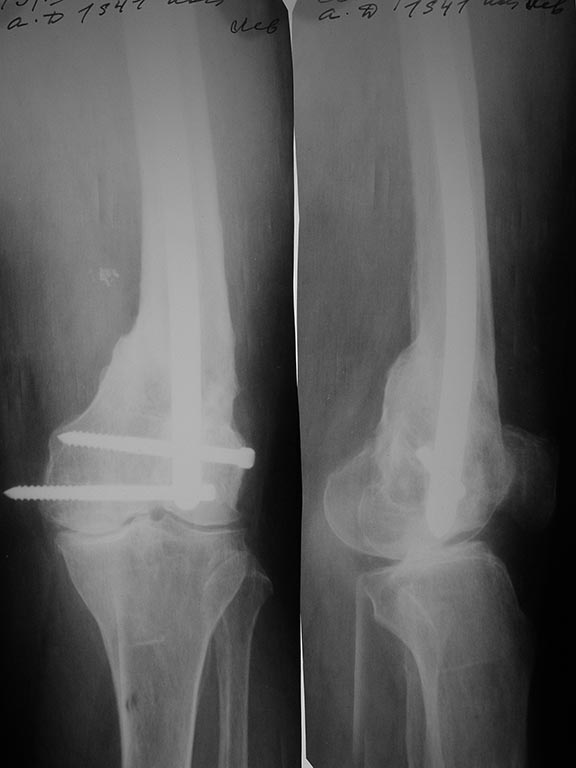

Здесь вполне можно не вмешиваться открыто. Сделать fixator-assisted nailing. Все закрыто убрать. Хорошо восстановить ось. Через медуллярный канал ручными развертками освежить концы отломков. И заштифтовать. Раз уже был ретроградный стержень - то ретроградно. Я бы взял большеберцовый гвоздь, чтобы ввести винты в разных плоскостях. Ну и гвоздь потолще, и винты 6 мм.

Вот давний пример похожего ложного сустава после неоднократных остеосинтезов.